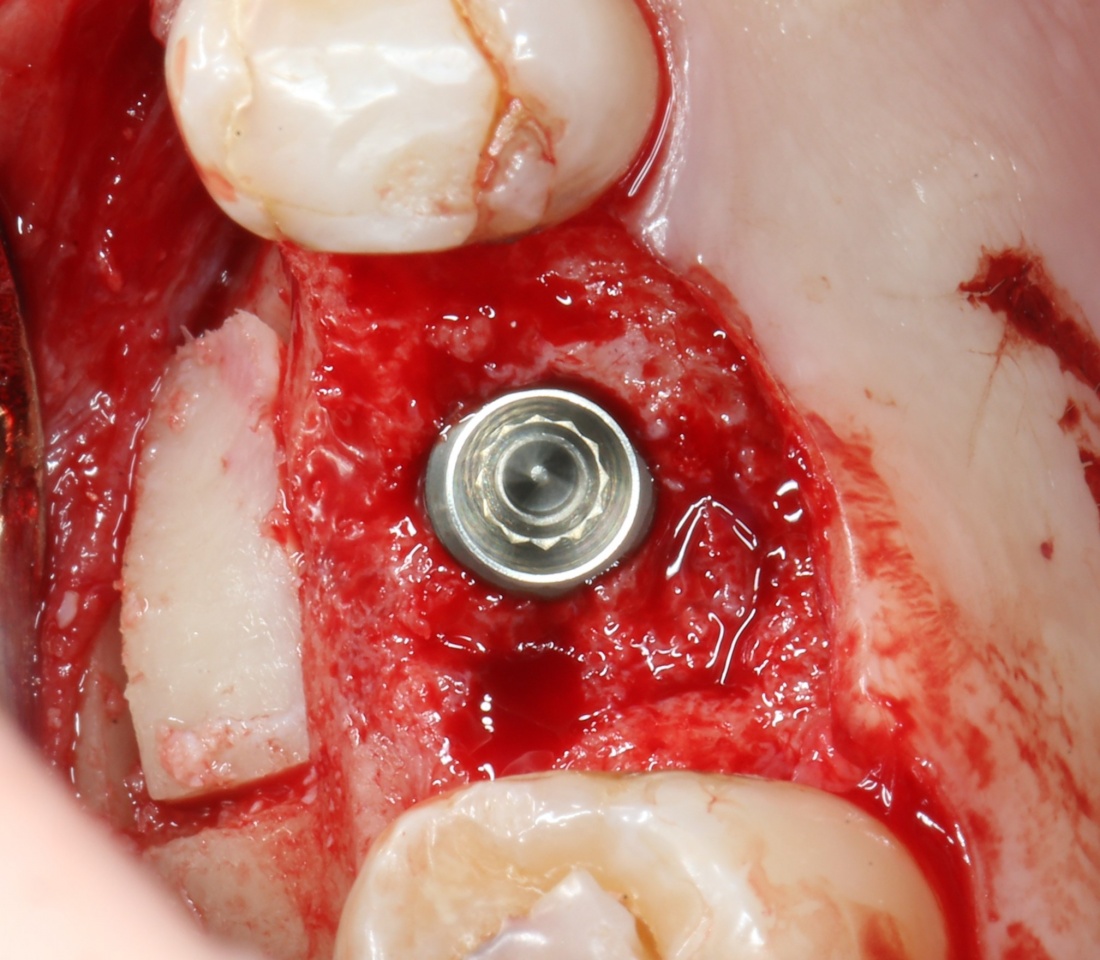

Приступаем к установке имплантата.

Кстати, комплект поставки не содержит ни заглушки, ни абатмента. А сам имплантат фиксируется на ключе простым заклиниванием платформы. Т. е. не слишком надёжно:

Если лунка подготовлена правильно, то имплантат проваливается в неё почти полностью: